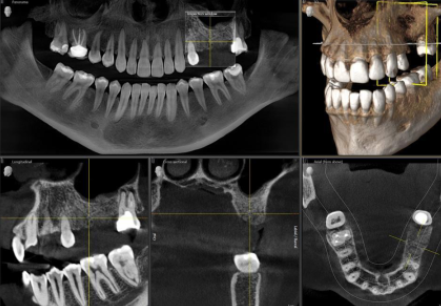

2. CBCT (Cone Beam Computed Tomography): A 3D View of the Airway

CBCT imaging has become the gold standard in airway diagnostics. Unlike traditional 2D X-rays, CBCT provides a high-resolution, three-dimensional view of the entire upper airway, soft tissues, and skeletal structures.

- Allows precise measurement of airway volume, identifying narrow or obstructed regions.

- Helps diagnose structural abnormalities, such as deviated septum, nasal obstructions, or enlarged tonsils.

- Assists in evaluating the relationship between jaw position and airway constriction.

- Plays a crucial role in planning maxillofacial surgeries and orthodontic interventions.

- Offers low radiation exposure compared to traditional CT scans.

CBCT scans are widely used in digital sleep medicine, orthodontics, and oral surgery to evaluate and manage airway-related conditions.

AI-driven algorithms can now automatically process cone beam computed tomography (CBCT) scans, segment the airway, and identify obstructions or narrowing regions with high precision. The ability to analyze skeletal and soft tissue structures in 3D allows clinicians to make more informed treatment decisions.

- Automated airway segmentation to measure volume and detect areas of restriction.